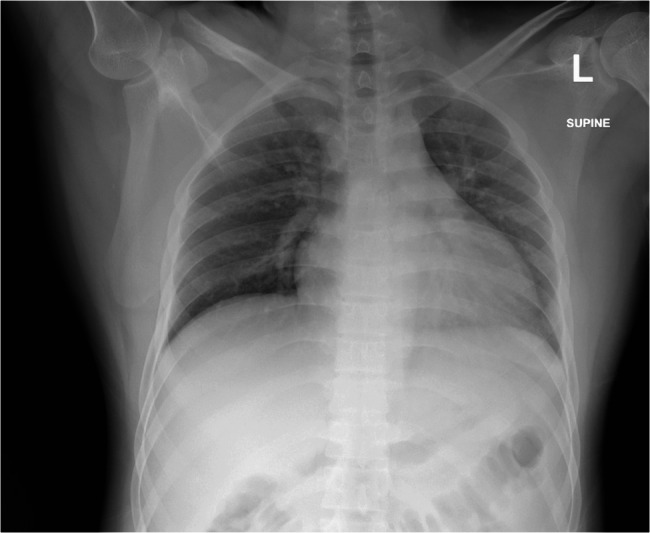

尽管在预防和治疗方面取得了进展,细菌性脑膜炎仍然是世界范围内发病率和死亡率的一个重要原因。及时诊断和适当的管理对患者的最佳预后至关重要。本病例报告描述了一名22岁的孟加拉国男性,因头痛、颈部疼痛、呕吐和左眼上睑下垂到急诊室就诊,最终被诊断为脑膜炎奈瑟菌脑膜炎。这个病例强调了罕见但重要的并发症动眼神经麻痹与这种感染有关。我们还发表了一篇文献综述,讨论了细菌性脑膜炎的发病率、病理生理学和脑神经受累的临床意义,重点是脑膜炎奈瑟菌,并探讨了细菌性脑膜炎和结核性脑膜炎重叠临床表现所带来的诊断挑战,特别是在资源有限的情况下。

Bacterial meningitis remains a significant cause of morbidity and mortality worldwide, despite advances in prevention and treatment. Prompt diagnosis and appropriate management are crucial for optimal patient outcomes. This case report describes a 22-year-old Bangladeshi male who presented to the emergency department with headache, neck pain, vomiting, and left eye ptosis, ultimately diagnosed with Neisseria meningitidis meningitis. This case highlights the rare but significant complication of oculomotor nerve palsy associated with this infection. We also present a literature review discussing the incidence, pathophysiology, and clinical implications of cranial nerve involvement in bacterial meningitis, focusing on N. meningitidis, and explore the diagnostic challenges posed by overlapping clinical presentations of bacterial and tuberculous meningitis, particularly in resource-limited settings.